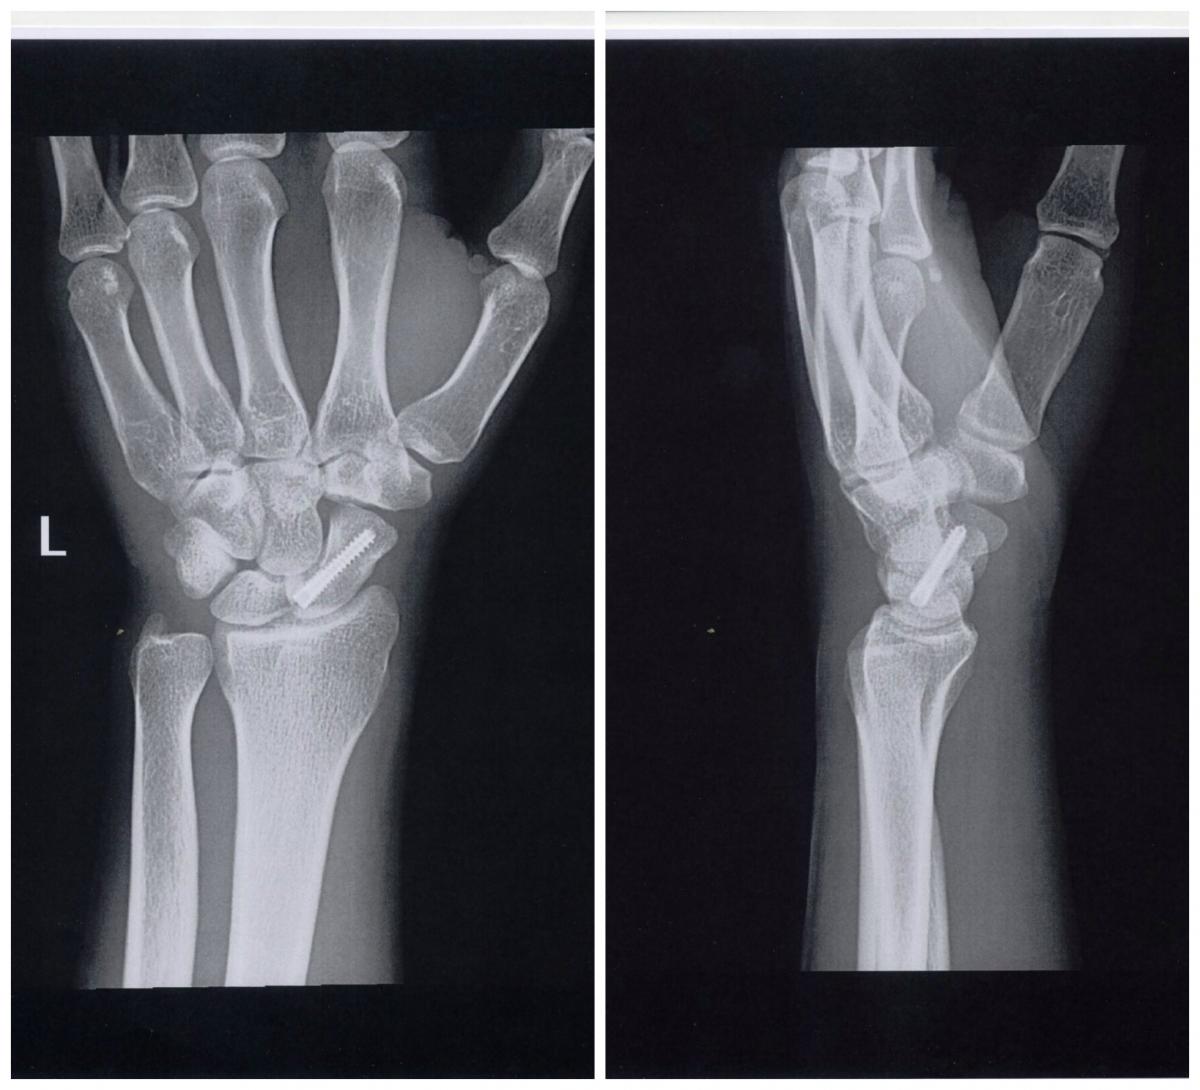

27 Nov 2015Hasta la consulta de Podoactiva Premier Madrid llegó un futbolista profesional con una fractura de escafoides de la mano izquierda. El escafoides es uno de los huesos pequeños de la muñeca con más probabilidad de fracturarse. Este hueso esté ubicado en el lado de la muñeca que corresponde al dedo pulgar.

El tratamiento de este tipo de fracturas puede requerir cirugía, o no. En el caso de nuestro paciente, se sometió a una cirugía percutánea, durante la cual se utilizó un implante metálico para mantener el escafoides en su lugar hasta que la fractura suelde por completo. Además, se inmovilizó la zona con una escayola.